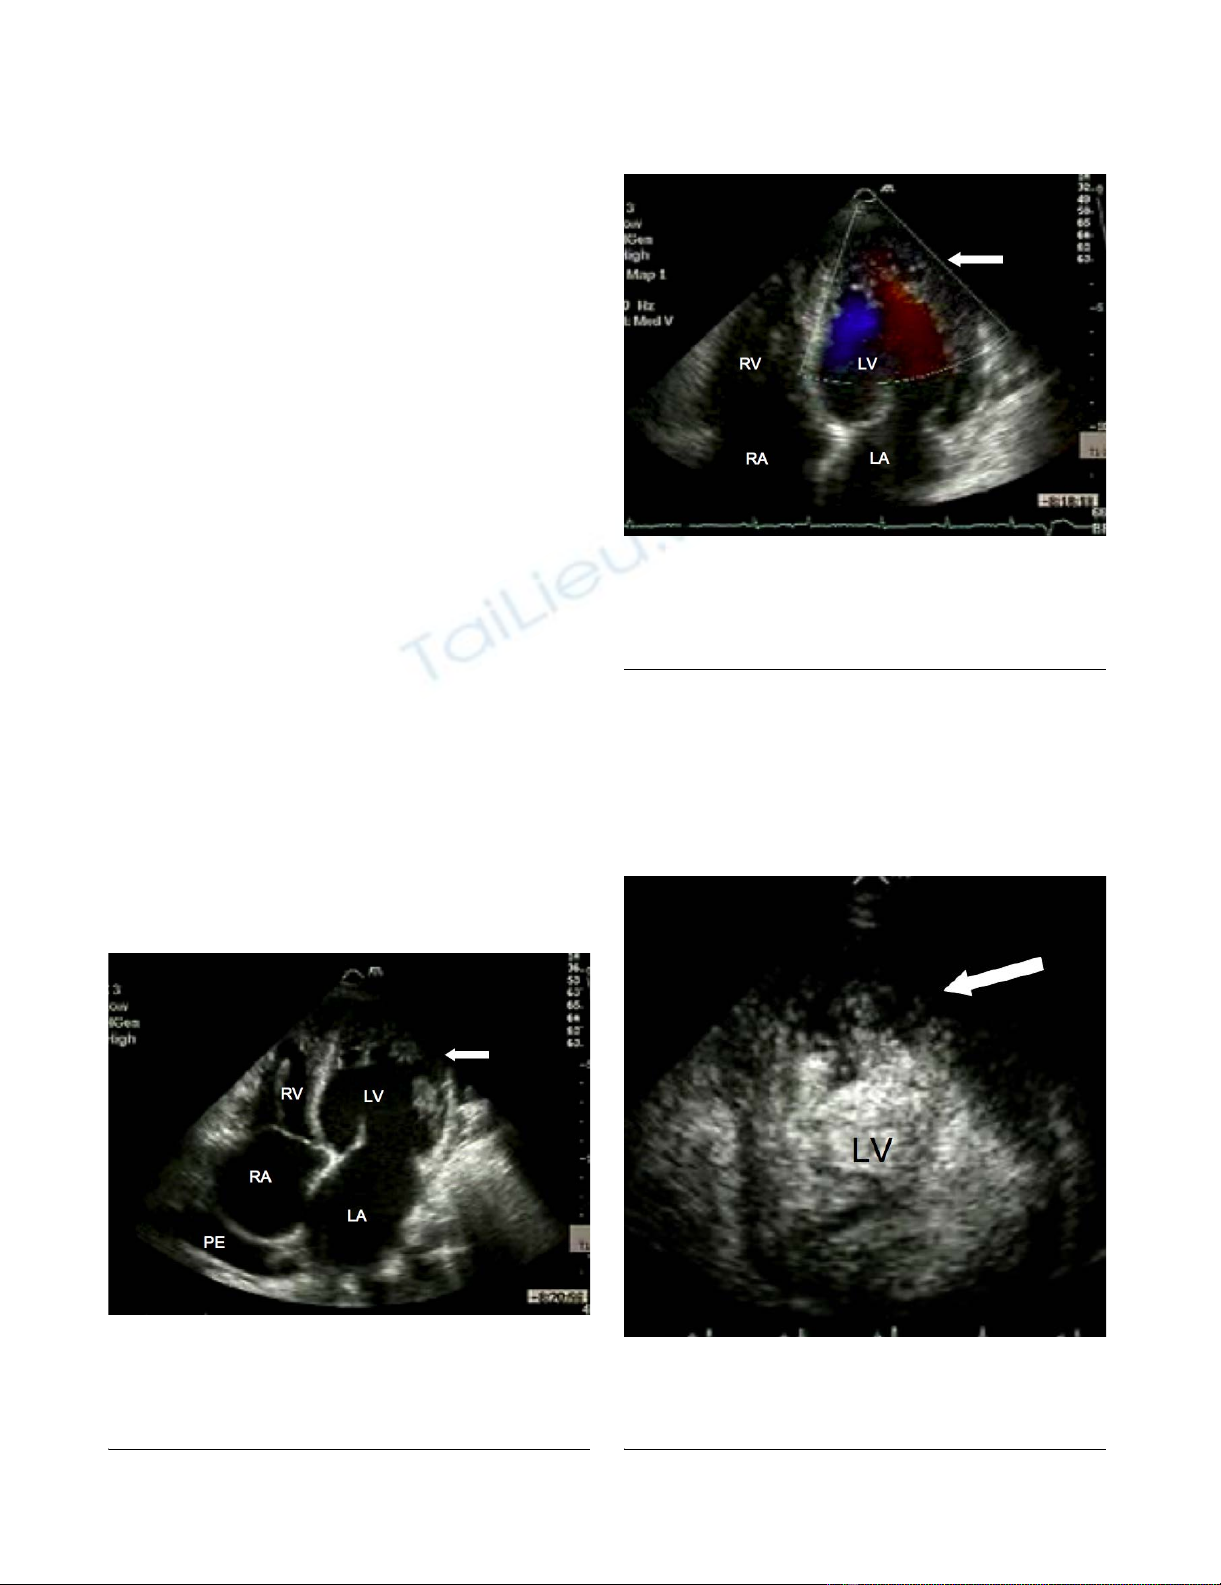

phy demonstrated a dilated left ventricle (end systolic

diameter 5.5 cm; end diastolic diameter 5.9 cm) with

severe systolic impairment and hypertrabeculation of the

left ventricular apex (Fig. 1) in the absence of significant

valvular heart disease. Doppler colour flow mapping con-

firmed colour flow between the trabeculations (Fig. 2).

Intravenous injection of ultrasound contrast agent con-

firmed an area of non-compacted myocardium subtend-

ing a thinner walled area of compaction and a diagnosis

of IVNC was made (Fig. 3).

Transthoracic echocardiographyFigure 1

Transthoracic echocardiography. Apical four chamber

view demonstrating marked trabeculation of the left ven-

tricular apex (arrow). RA, right atrium; LA, left atrium; LV,

left ventricle; RV, right ventricle; PE, pleural effusion.

Transthoracic echocardiographyFigure 2

Transthoracic echocardiography. Doppler colour flow

mapping suggesting blood flow present between the ventricu-

lar trabeculations (arrow). RA, right atrium; LA, left atrium;

LV, left ventricle; RV, right ventricle.

Transthoracic echocardiographyFigure 3

Transthoracic echocardiography. Following intravenous

injection, contrast agent is visualised between the ventricular

trabeculations (arrow). LV, left ventricle.